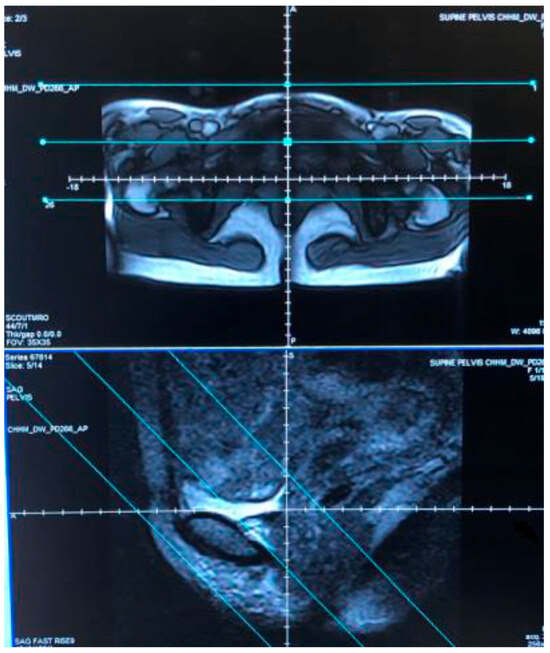

3.1. Scout Images

The first step in the imaging of each yoga posture was to take scout images to ensure that the anatomic region of interest within the pelvis where the bladder and the course of the urethra are centered was within the field of the scanner (Figure 2).

Figure 2. Scout images: The two scans show examples of axial (upper) and sagittal (lower) scout images which were the first element of each scan sequence. The blue lines indicate the field of view used to ensure the entire bladder and full length of the urethra are included in the protocol.